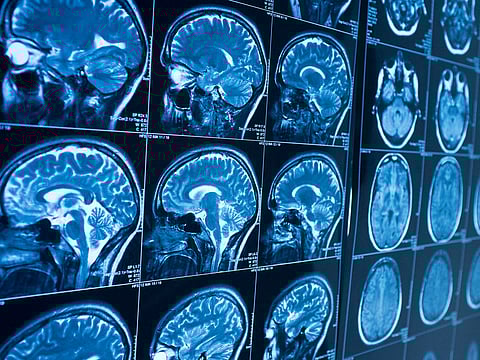

Even mild cases of COVID-19 may lead to loss of brain tissue, according to findings from a long-term study involving 782 volunteers. As part of the ongoing UK Biobank study, participants underwent brain scans before the pandemic.

For a before-and-after comparison, researchers invited 394 COVID-19 survivors to come back for follow-up scans as well as 388 healthy volunteers. Most of the COVID-19 survivors had only mild-to-moderate symptoms, or no symptoms at all, while 15 had been hospitalised.

Among the COVID-19 survivors, researchers saw "significant" loss of gray matter in regions of the brain related to smell and taste - the left parahippocampal gyrus, left orbitofrontal cortex and left insula. Some of the affected brain regions are also involved in the memory of experiences that evoke emotional reactions, the researchers noted in a report posted on medRxiv on Tuesday ahead of peer review. The changes were not seen in the group that had not been infected.